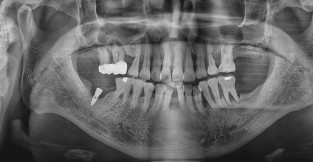

임플란트 재수술

치료기간 : 2024-03-21 ~ 2024-07-26

1. 상기 x-ray 이미지 모두 동일한 해당 의료기관에서 진료한 환자입니다.

2. 상기 x-ray 이미지 모두 동일 인물의 것입니다.

3. 치료 전 이미지는 2024-03-21에 촬영했으며, 치료 후 이미지는 2024-07-26에 촬영하였습니다.

4. 상기 x-ray 이미지 모두 동일 조건에서 환자분의 동의를 받아촬영되었습니다.

* 임플란트 시술은 환자분의 상태(고혈압, 당뇨 등)에 따라 부작용이 있을 수 있으니, 반드시 전문의와 상담이 필요합니다.

* 임플란트 수술 부작용

: 수술 후 출혈, 교합, 통증, 붓기, 염증 등의 문제점이 발생할 수 있습니다.)